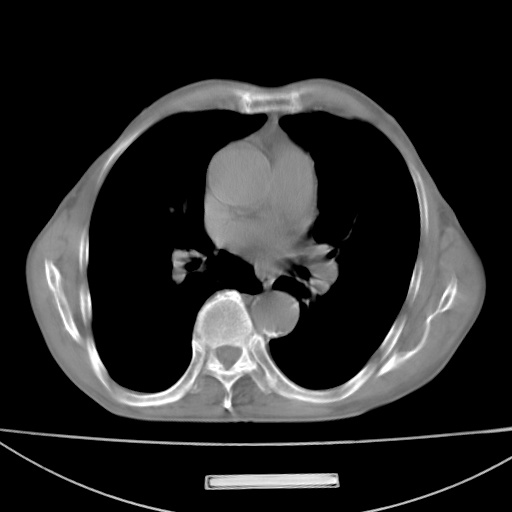

标题: CT13796:请会诊右上费病变!

患者男80岁,反复咳嗽多年,咳喘伴咯血1月

右上肺周围型肺癌伴肺门淋巴结转移.右上肺继发型肺结核.

右上肺周围型肺癌伴肺门淋巴结转移

右肺上叶占位性病变,考虑周围型肺癌,肺门淋巴结转移。要是能提供更多的临床资料就好了,以供鉴别诊断。

右肺上叶占位性病变,考虑周围型肺癌,肺门淋巴结转移。

考虑为:右肺上叶肺癌伴阻塞性肺炎、右肺门及纵膈淋巴结转移。